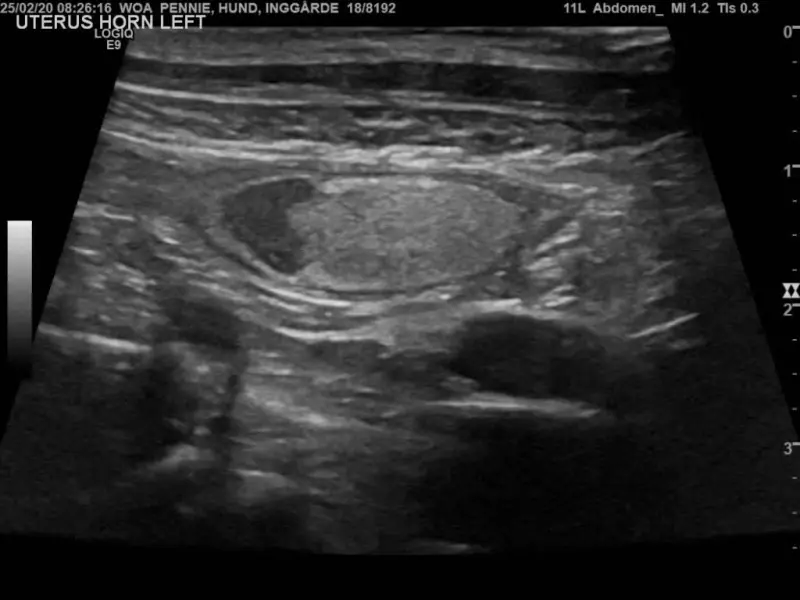

Kolejny epizod koprostazy wystąpił w 2020 r. Ponownie stwierdzono w USG obecność torbieli wypełnionej echogennym płynem, wielkości ok. 5 × 2 cm. Zastosowano identyczne leczenie jak poprzednio. Usunięto zawartość torbieli, którą określono jako ropień, torbiel przepłukano roztworem fizjologicznym. Ponownie wykonano cytologię i posiew – nie wykryto bakterii.